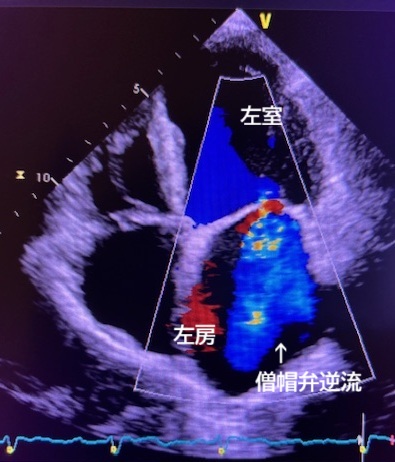

超音波検査は、どなたでも安心して繰り返し受けることができる検査です。甲状腺、乳腺、心臓、腹部、胎児、血管などを対象とし、臓器の形、大きさ、血液の流れ方を観察します。当検査室で最も行われている検査は、心臓超音波(心エコー)検査です。心エコー検査は、経胸壁心エコーと経食道心エコーがあり、経胸壁心エコーでは、胸にゼリーをぬり、探触子(プローブ)をあてることで、心臓の大きさ、壁の厚さ、弁(血液の流れを制御しています)の動き方を確認し、疾患の有無・重症度を診断します。不整脈、弁膜症、先天性心疾患等が対象となりますが、手術前後評価も行います。更に詳細な検査である経食道心エコーは、医師と共に行います。細い管を口から挿入し、2Dや3D画像で心臓内を観察し、手術の必要性等の判断が行われます。この検査では、苦痛を和らげるため、鎮静剤を使用して検査を行うことがあります。